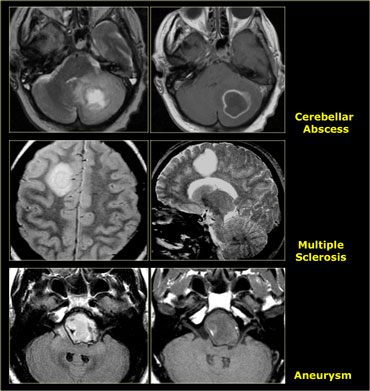

Finally we have to consider the possibility that we are dealing with a lesion that simulates a tumor - like an abscess, MS-plaque, vascular malformation, aneurysm or an infarct with luxury perfusion.

Tumor Mimics

Many non-tumorous lesions can mimic a brain tumor.

Abscesses can mimic metastases.

Multiple sclerosis can present with a mass-like lesion with enhancement, also known as tumefactive multiple sclerosis..

In the parasellar region one should always consider the possibility of a aneurysm.

Infections and vascular lesions can also mimic a CNS tumor.